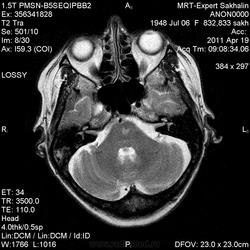

А мне постконтрастные не нравятся - ну не укладываются они в ОДЭМ и в ОНМК.

О.С., я согласен, что контрастирование нехарактерно для ОНМК, ведь в подострую стадию инфаркта наблюдается, как правило, гиральный тип усиления. Плюс, на ОНМК непохоже то, что поражено почти только белое вещество, а кора интактна. И потом, при такой локализации инфаркта обязательно должна быть яркая клиника, и уж никак не только "головная боль".

А где вы видите постконтрастные, пардон, изображения? Это натив.

Постконтрастные сканы есть.После надписи"постконтраст".

тогда да, не особо в геморрагический ОНМК укладывается

Как вариант хочу предложить на рассмотрение грибковое поражения головного мозга или токсоплазмоз. В таком случае полностью укладывается изменение сигнальных характеристик и на нативе и на постконтрастных сканах. Можно проверить на иммуносупресивные состояния, на наличие грибкового эндокардита (Узи сердца).

На опухоль не тянет. Для инфаркта и банальной гемморрагии не характерен тип накопления контраста на мой взгляд.

На динамике видно что это был действительно ОНМК - сомнений нет, данных за объем не вижу.